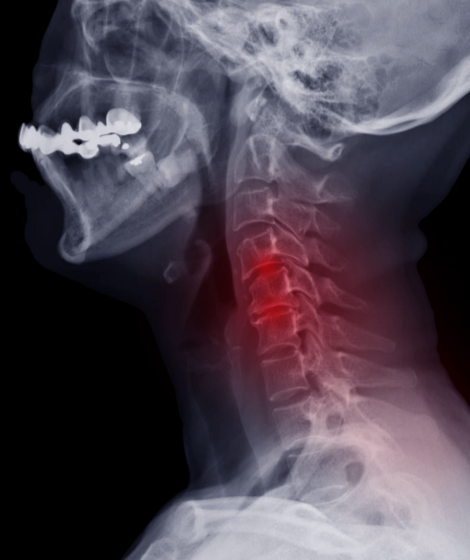

In the case of cervical myelopathy, the spinal cord that passes through the cervical spine (i.e. neck) portion of the spinal cord is compressed, impairing transmission of nerve signals to and from the arms, chest, legs, pelvis, and abdomen as rapidly as it should.

Degenerative changes that occur with conditions such as arthritis can affect the ligaments, discs, and joints in the spine. These changes put pressure on the spinal cord by compressing it or causing the cord to become narrowed. This narrowing of the cervical spinal cord is called cervical stenosis. When the cervical spine becomes too tight, it compresses the spinal cord. This leads to the symptoms of myelopathy.

A good clinical exam can usually detect the signs of cervical myelopathy. The examination often includes imaging studies such as MRIs or CT scans of the cervical spine. These studies may reveal a narrowing of the spinal canal in the neck or a compression of the spinal cord, indicating the possibility of cervical myelopathy. Somatosensory evoked potential (or SSEP) studies to measure how fast nerve signals move through the spinal cord may also be used in determining the diagnosis.